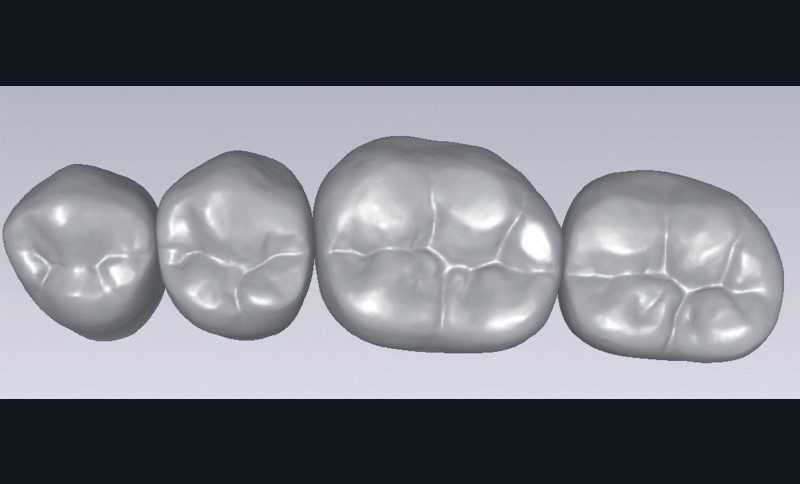

que = prothèse complète. Cette idée préconçue n’est plus vraie. De nos jours, la prothèse gériatrique se décline sur tous les types de prothèses amovibles, y compris les appareils complets implanto-retenus. Ceci signifie que les prothésistes dentaires, mais aussi les fabricants de dents prothétiques, sont confrontés à de nouveaux défis (fig. 1 à 4).